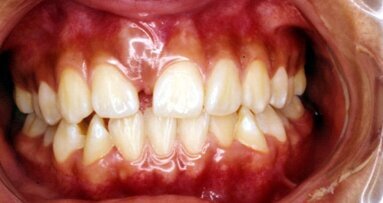

Caso clinico

- Paciente femenino.

- anos de edad.

- Condiciones generales de salud medica buenas.

- Problemas estéticos sector anterior.

- Endodoncia y perno metálico en el 22.

Plan de tratamiento:

- Cuatro coronas en Zircornia.